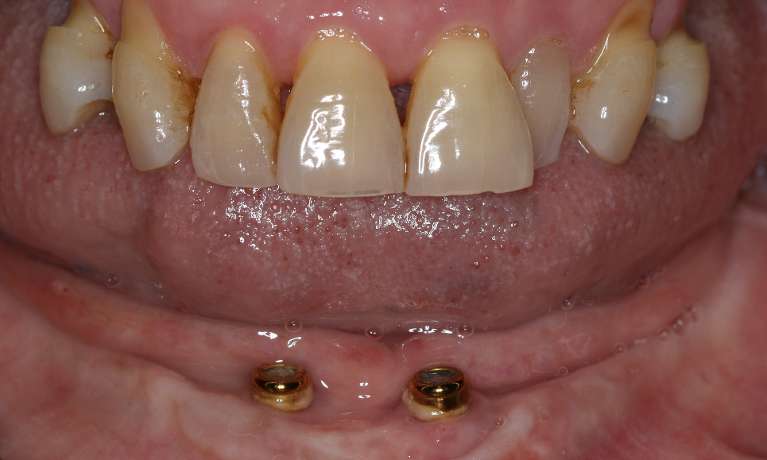

The upper and lower sets of teeth are removed and replaced with removable dentures that are securely held in place by dental implants. This provides improved stability, comfort, and function - leading to a patient who was thrilled with their new smile!

Implant-retained dentures have transformed our patient's smile. This permanent solution provides stability, comfort and a natural look, making it a fantastic option for those missing teeth. Our patient is thrilled with the results - and we are too.

Implant-retained dentures have given this patient a smile that's built to last. This permanent solution not only looks natural but also provides the comfort and security needed to enjoy life to the fullest.